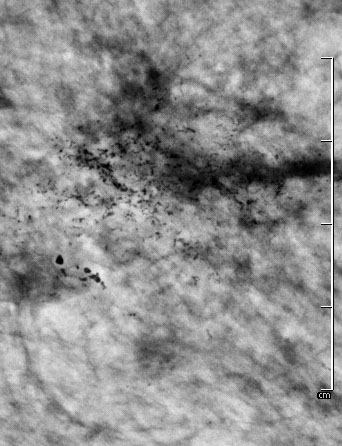

Durch die höhere Kontrastauflösung bei einem höheren Kontrast-Rausch-Verhältnis wird die Erkennungsrate von malignitätsverdächtigen Veränderungen deutlich verbessert. Der Radiologe kann auf hochauflösenden 5 MP-Monitoren die Dichte, Form und Kontur von Gewebearealen wesentlich exakter differenzieren und so gutartige von bösartigen Herdbefunden sicherer unterscheiden. Im Speziellen sind Mikroverkalkungen auch bei der dichten Brust besser zu analysieren.

40 % der Mammakarzinome weisen Mikroverkalkungen auf. Mikrokalzifikationen sind auch bei sehr dichtem Brustgewebe immer sichtbar. Eine Mammographie sollte daher ab dem 40. Lebensjahr die primäre Untersuchungsmethode sein.